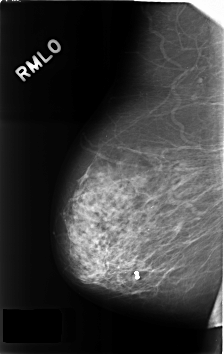

ics_version 1.0 filename C-0287-1 DATE_OF_STUDY 9 1 1995 PATIENT_AGE 89 FILM FILM_TYPE REGULAR DENSITY 2 DATE_DIGITIZED 4 8 1998 DIGITIZER LUMISYS LASER SEQUENCE LEFT_CC LINES 4592 PIXELS_PER_LINE 2960 BITS_PER_PIXEL 12 RESOLUTION 50 OVERLAY LEFT_MLO LINES 4584 PIXELS_PER_LINE 2976 BITS_PER_PIXEL 12 RESOLUTION 50 OVERLAY RIGHT_CC LINES 4568 PIXELS_PER_LINE 2928 BITS_PER_PIXEL 12 RESOLUTION 50 NON_OVERLAY RIGHT_MLO LINES 4600 PIXELS_PER_LINE 2904 BITS_PER_PIXEL 12 RESOLUTION 50 NON_OVERLAY |